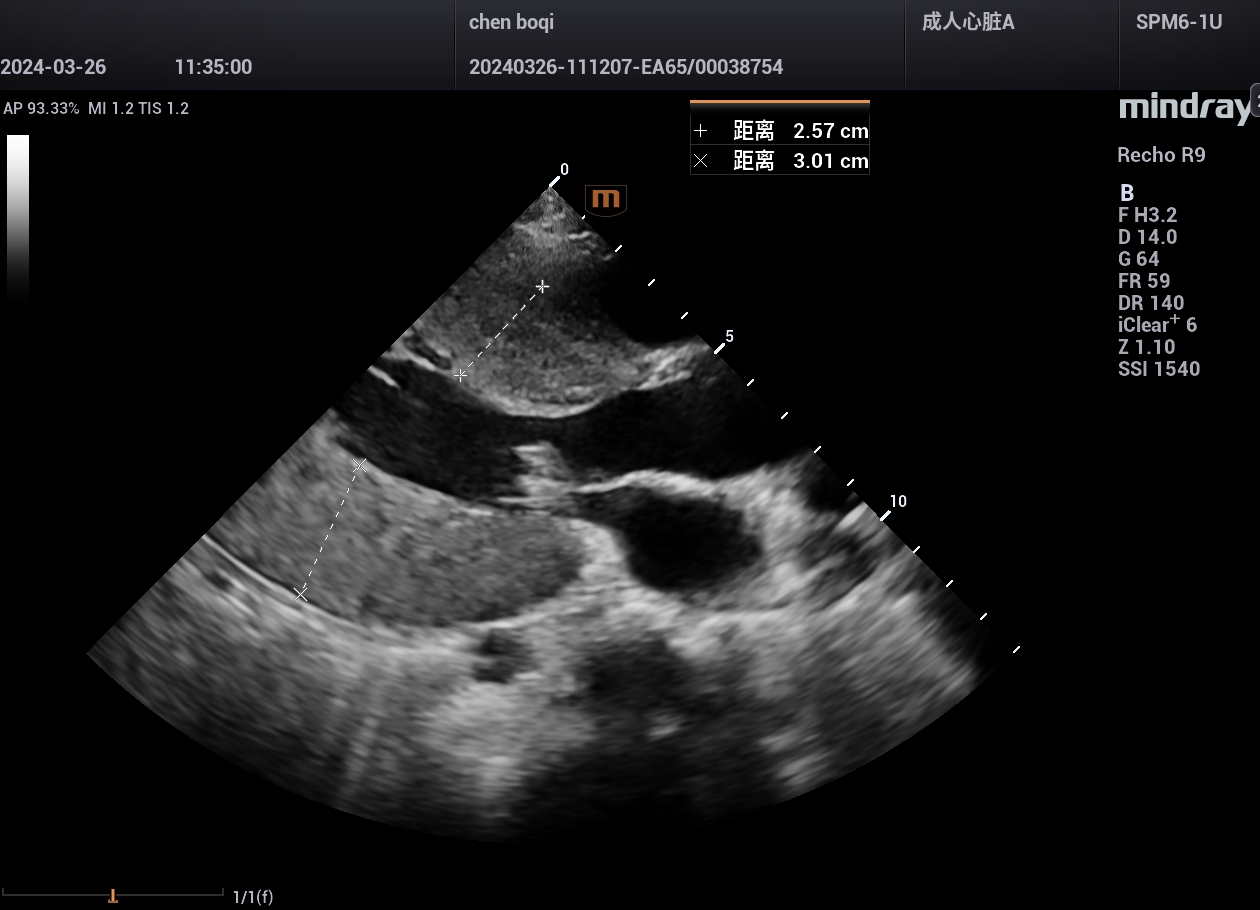

病例,肥厚梗阻性心肌病,10岁小孩,典型病例。迈瑞Recho R9,2024年3月

高端心脏超声迈瑞Recho R9,实现县县超声事业的高质量发展!